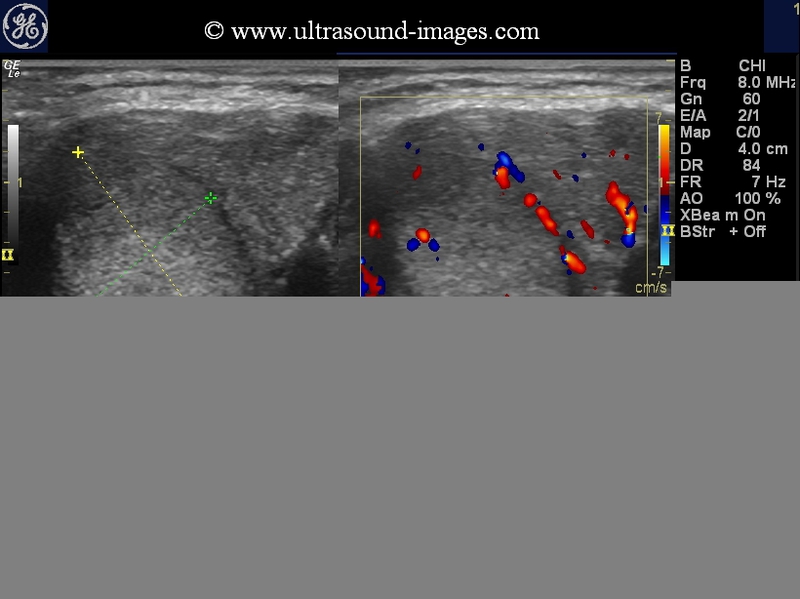

Hyperthyroidism-Graves-disease

These ultrasound/ color doppler images (taken with a Nemio-XG color doppler scanner), reveal markedly increased vascualrity throughout the thyroid gland. Some degree of inhomogeneity is also present. The patient was a middle aged female with typical features of thyrotoxicosis. Ultrasound images are diagnostic of hyperthyroidism.

thyrotoxicosis-case-2

Another example of a young woman with hyperthyroidism. Observe the diffusely enlarged, inhomogenous thyroid with marked vascularity on color Doppler ultrasound- the so called thyroid inferno.